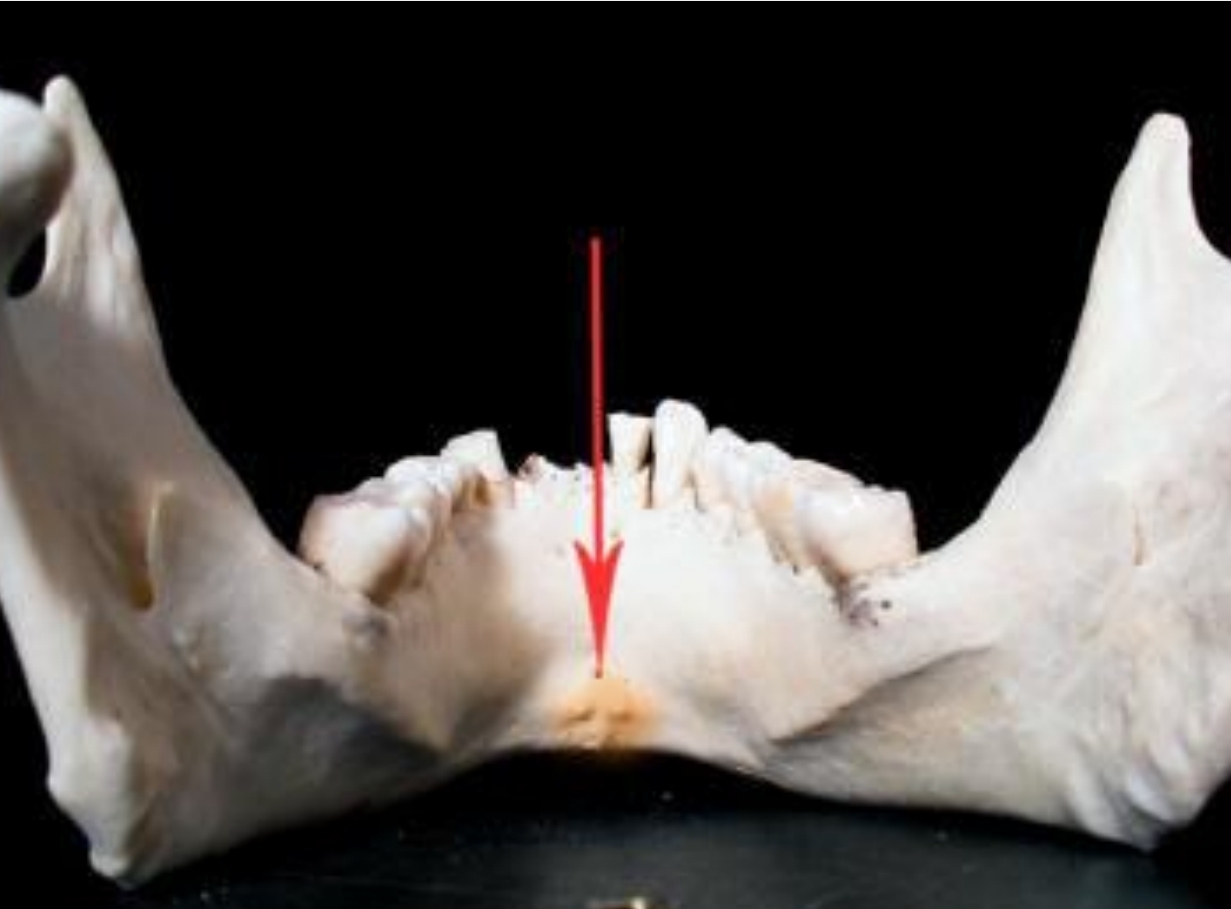

2 rolls of bone on lingual surface of anterior teeeth

Genial Tubercles